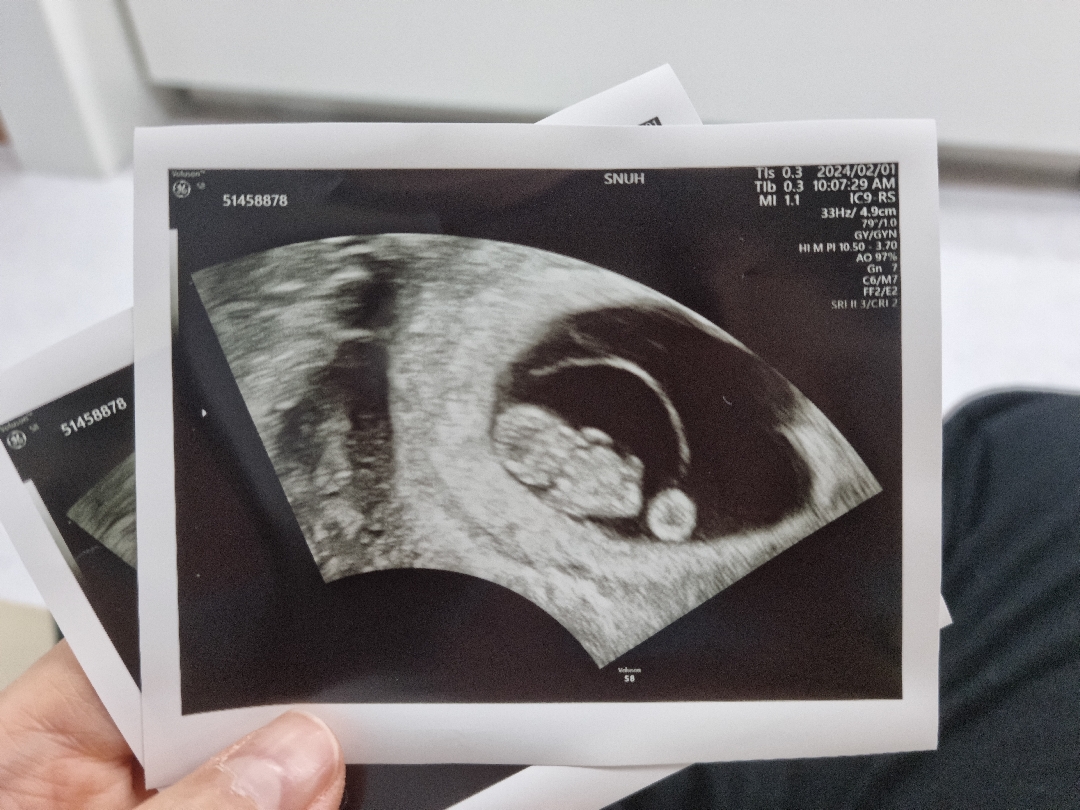

1.81cm 귀여운 젤리곰을 만나고 왔어요. 만성질환으로 고위험 산모지만,, 잘 이겨내고 큰 이벤트 없이 만날 수 있기를 기도해봅니다.

8주6일차예요.♡